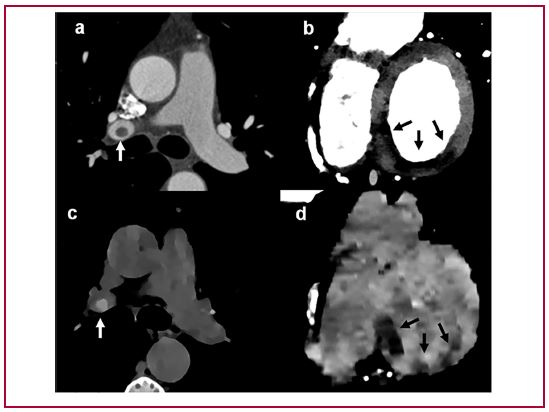

Detección de tromboembolismo pulmonar e infarto de miocardio por medio de densidad de electrones sin contraste